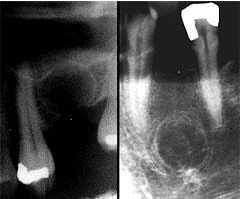

Корневые кисты – это рентгенопрозрачные капсулы с четкими границами, размеры которых варьируются от 2-3 мм до 2-3 см. В большинстве случаев они развиваются бессимптомно, если не осложнены вторичным воспалением. Даже крупные образования не вызывают смещения зубов или расширения костной ткани.

Остаточная киста легко обнаруживается на рентгеновском снимке. Размеры варьируются от нескольких миллиметров до нескольких сантиметров.

Киста в десне развивается из фолликулярного мешочка, окружающего непрорезавшийся зуб. На рентгеновском снимке выглядит как капсула, чаще всего расположенная вокруг коронки такого зуба. Может вызывать значительные повреждения зуба, характеризуется быстрым ростом, способным смещать соседние зубы и приводить к расширению кортикальной пластинки.

Точные причины ее появления пока не установлены. Она редко достигает крупных размеров, четко видна на рентгеновском снимке и обычно располагается рядом с боковой поверхностью корня зуба. Зубы, связанные с такими кистами, чаще всего сохраняют нормальную пульпу.

Их этиология также до конца не установлена. Такие кисты могут быть обнаружены в любой части опорной поверхности челюстей, но чаще всего в нижней. Морфологически они имеют разнообразные формы. На рентгеновских снимках они четко видны и могут содержать различные помутнения в зависимости от степени кальцификации новообразования. После постановки диагноза лечение включает хирургическое выскабливание или резекцию.